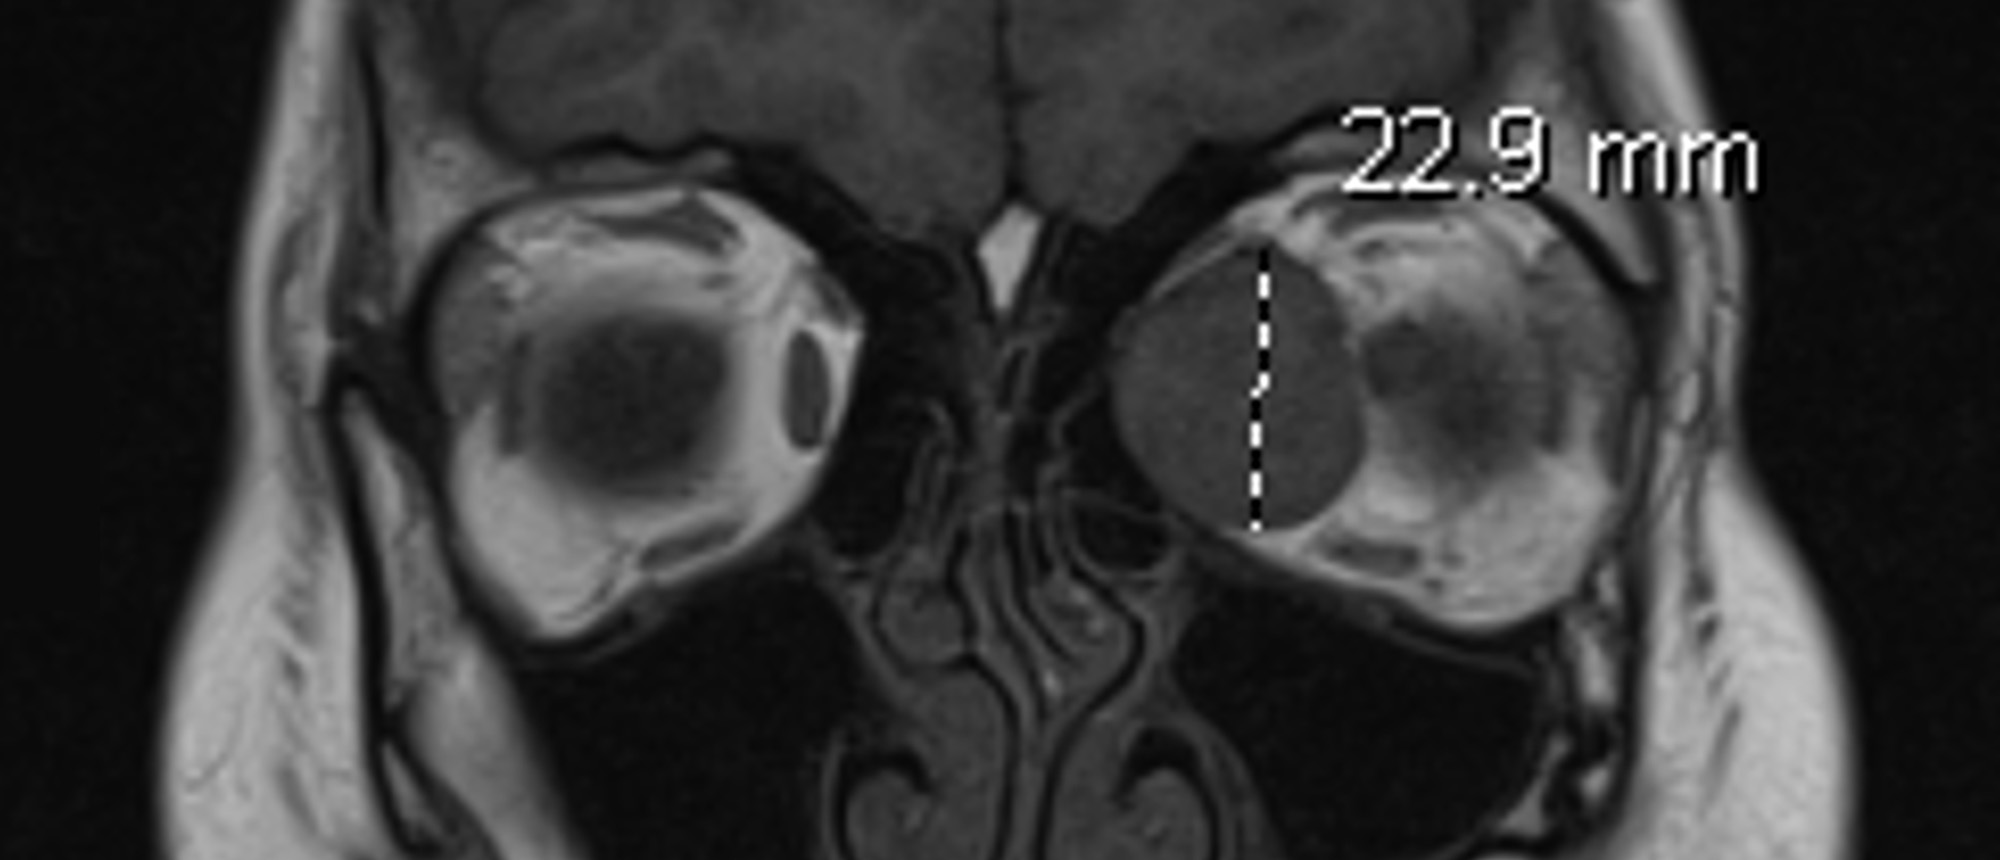

Abstract A patient presented to the Bascom Palmer Eye Institute with blurred vision in the left eye for 5 days. Past medical and ocular history was unremarkable. Past social history was notable for 25 pack-year smoking history. Visual acuity in the right eye was 20/20. Visual acuity in the left eye…

Choroidal Metastasis A patient presented to the Bascom Palmer Eye Institute with blurred vision in the left eye for 5 days. Past medical and ocular history was unremarkable. Past social history was notable for 25 pack-year smoking history. Visual acuity in the right eye was 20/20. Visual acuity in …